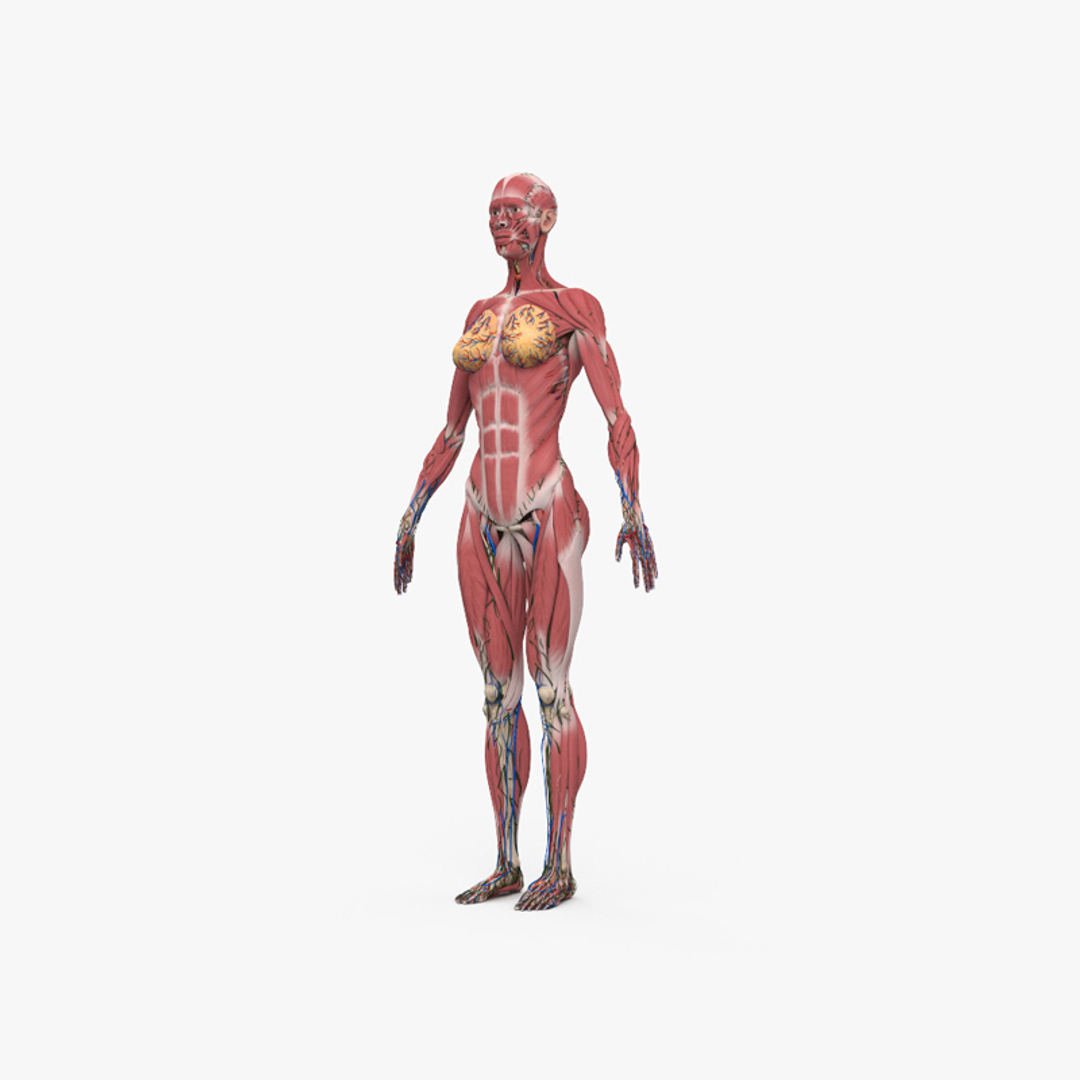

www.etsy.comComplete Female Anatomy 3D Model - TurboSquid 1743712

www.etsy.comComplete Female Anatomy 3D Model - TurboSquid 1743712

www.turbosquid.comanatomy turbosquid

www.turbosquid.comanatomy turbosquid